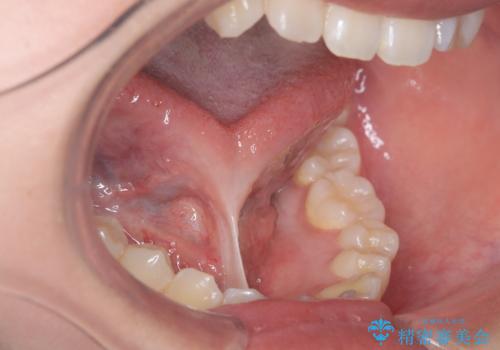

舌小帯切除術を行い舌の可動域を広げ、滑舌の向上を目指しました。

短い舌小帯に舌が引っ張られて舌がハート型になっています。

治療後、舌の可動域がかなり広がり患者様に大変ご満足していただけました。